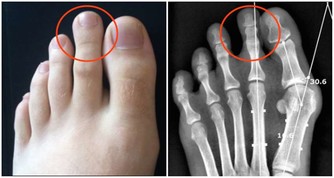

因皮脂腺阻塞或外力穿刺傷而形成,通常鼓起的表皮中心會看到一個小黑孔,看起來和青春痘有點像,

究竟粉瘤到底是什麼呢?根據元氣網報導,粉瘤是常見的皮下腫塊疾病,這個真的要注意!分享出去讓更多人知道吧!

因此若一發現長有粉瘤,最好盡快就醫,治療方式通常採取藥物注射、雷射治療、切開引流、手術摘除等視狀況而定,

越早​​治療,疤痕越小,復原也越快。

但粉瘤不會自行消退,可能隨時間愈長愈大。